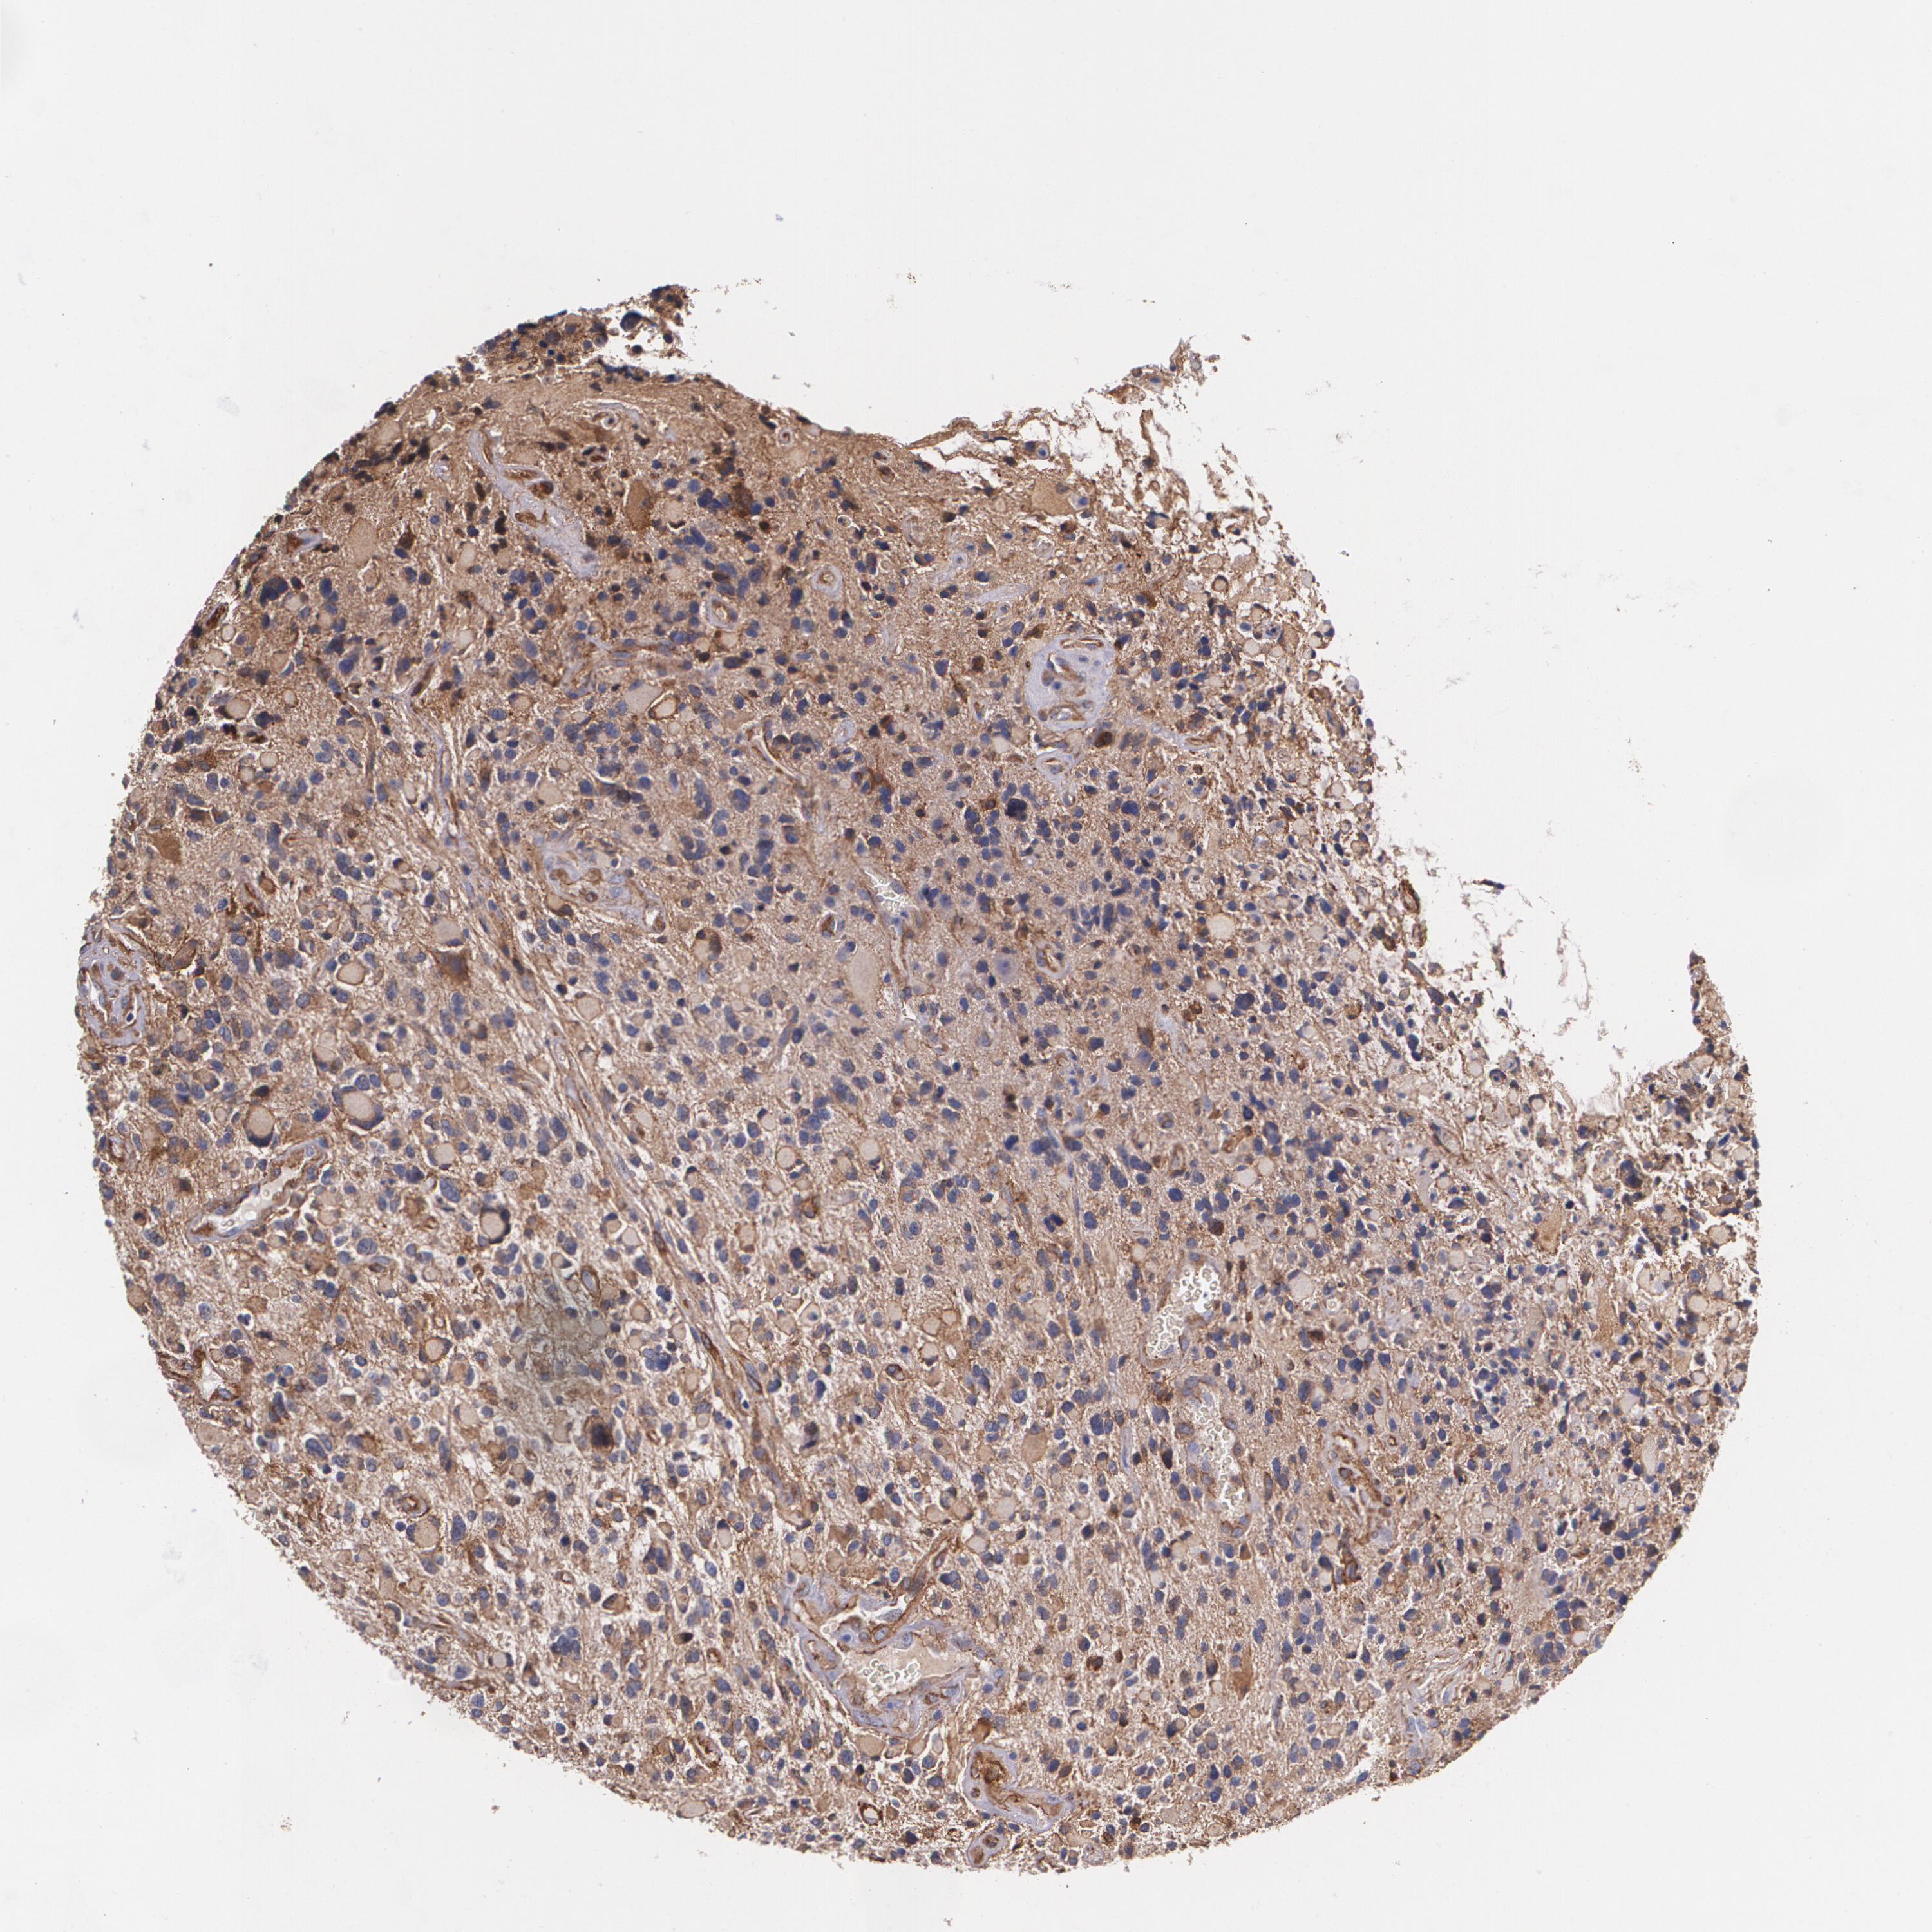

GLIOMA - Protein expressioni

A mouse-over function shows sample information and annotation data. Click on an image to view it in a full screen mode. Samples can be filtered based on level of antibody staining by selecting one or several of the following categories: high, medium, low and not detected. The assay and annotation is described here.

Note that samples used for immunohistochemistry by the Human Protein Atlas do not correspond to samples in the TCGA dataset.

Antibody stainingi

Antibody staining in the annotated cell types in the current human tissue is reported as not detected, low, medium, or high, based on conventional immunohistochemistry profiling in selected tissues. This score is based on the combination of the staining intensity and fraction of stained cells.

Each image is clickable and will lead to virtual microscopy that enables deeper exploration of all samples and also displays staining intensity scores, fraction scores and subcellular localization as well as patient and tissue information for each sample.

Antibody HPA001636

Antibody HPA001637

Antibody CAB010822

Staining

High

Medium

Low

Not detected

Intensity

Strong

Moderate

Weak

Negative

Quantity

>75%

75%-25%

<25%

None

Location

Nuclear

Cytoplasmic/membranous

Cytoplasmic/membranous,nuclear

Glioma, malignant, High grade

Glioma, malignant, Low grade

Glioma, malignant, NOS